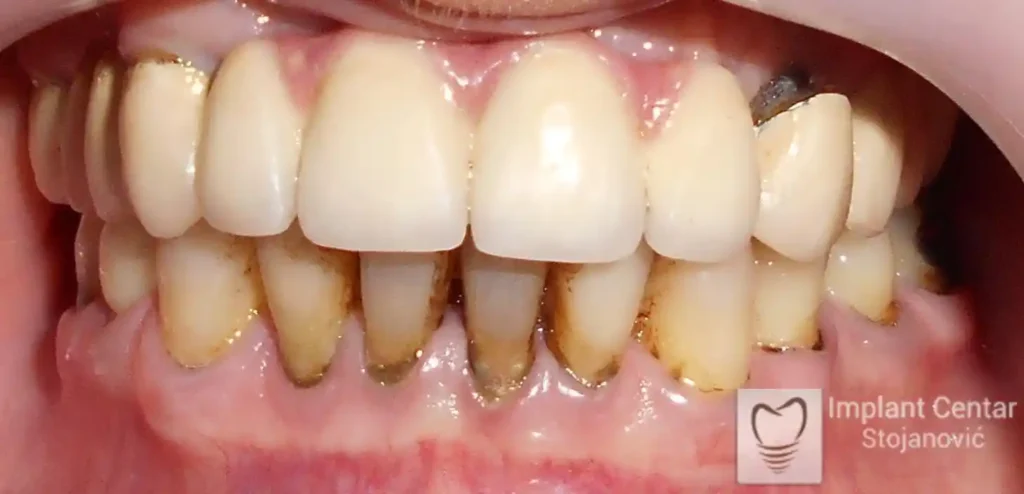

Pacijent sa rascepom usne, nepca i alveolarnog grebena uspešno je rehabilitovan fiksnim protetskim radom na implantatima. Pre dolaska u našu ordinaciju, pacijent je u gornjoj vilici nosio totalnu protezu preko preostalih zuba, dok je u donjoj vilici bio zbrinut parcijalnom mobilnom protezom. Tokom višegodišnje potrage za adekvatnim rešenjem, pacijent nije uspeo da pronađe zadovoljavajuću terapijsku opciju ni u zemlji ni u inostranstvu.

Nakon detaljnog kliničkog pregleda i analize radioloških snimaka, izrađen je sveobuhvatan plan terapije sa ciljem uklanjanja mobilnih proteza i postizanja maksimalne funkcionalne i estetske rehabilitacije. Zbog loše biološke vrednosti preostalih zuba, doneta je odluka o njihovom vađenju i ugradnji dentalnih implantata.

Poseban terapijski izazov predstavljalo je premošćavanje defekta nastalog usled rascepa, kao i ograničena količina raspoložive kosti u gornjoj vilici. Primenom većeg broja implantata i odgovarajućih procedura nadoknade kosti, postignuta je stabilna osnova za fiksni protetski rad.

Tokom perioda oseointegracije, pacijent je bio zbrinut fiksnim privremenim krunicama, čime je već pet dana nakon intervencije obezbeđena potpuna funkcionalna i estetska rehabilitacija. Nakon završetka perioda integracije implantata, izrađeni su definitivni cirkonijum-keramički mostovi na implantatima.

Pacijent je izuzetno zadovoljan postignutim rezultatom, navodeći da po prvi put jasno oseća svoje nepce tokom žvakanja, kao i da se smeje sa punim samopouzdanjem.